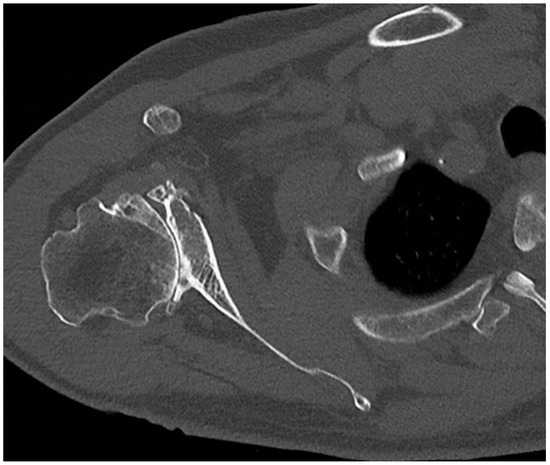

4. Preoperative Time: CT Scan and Planning